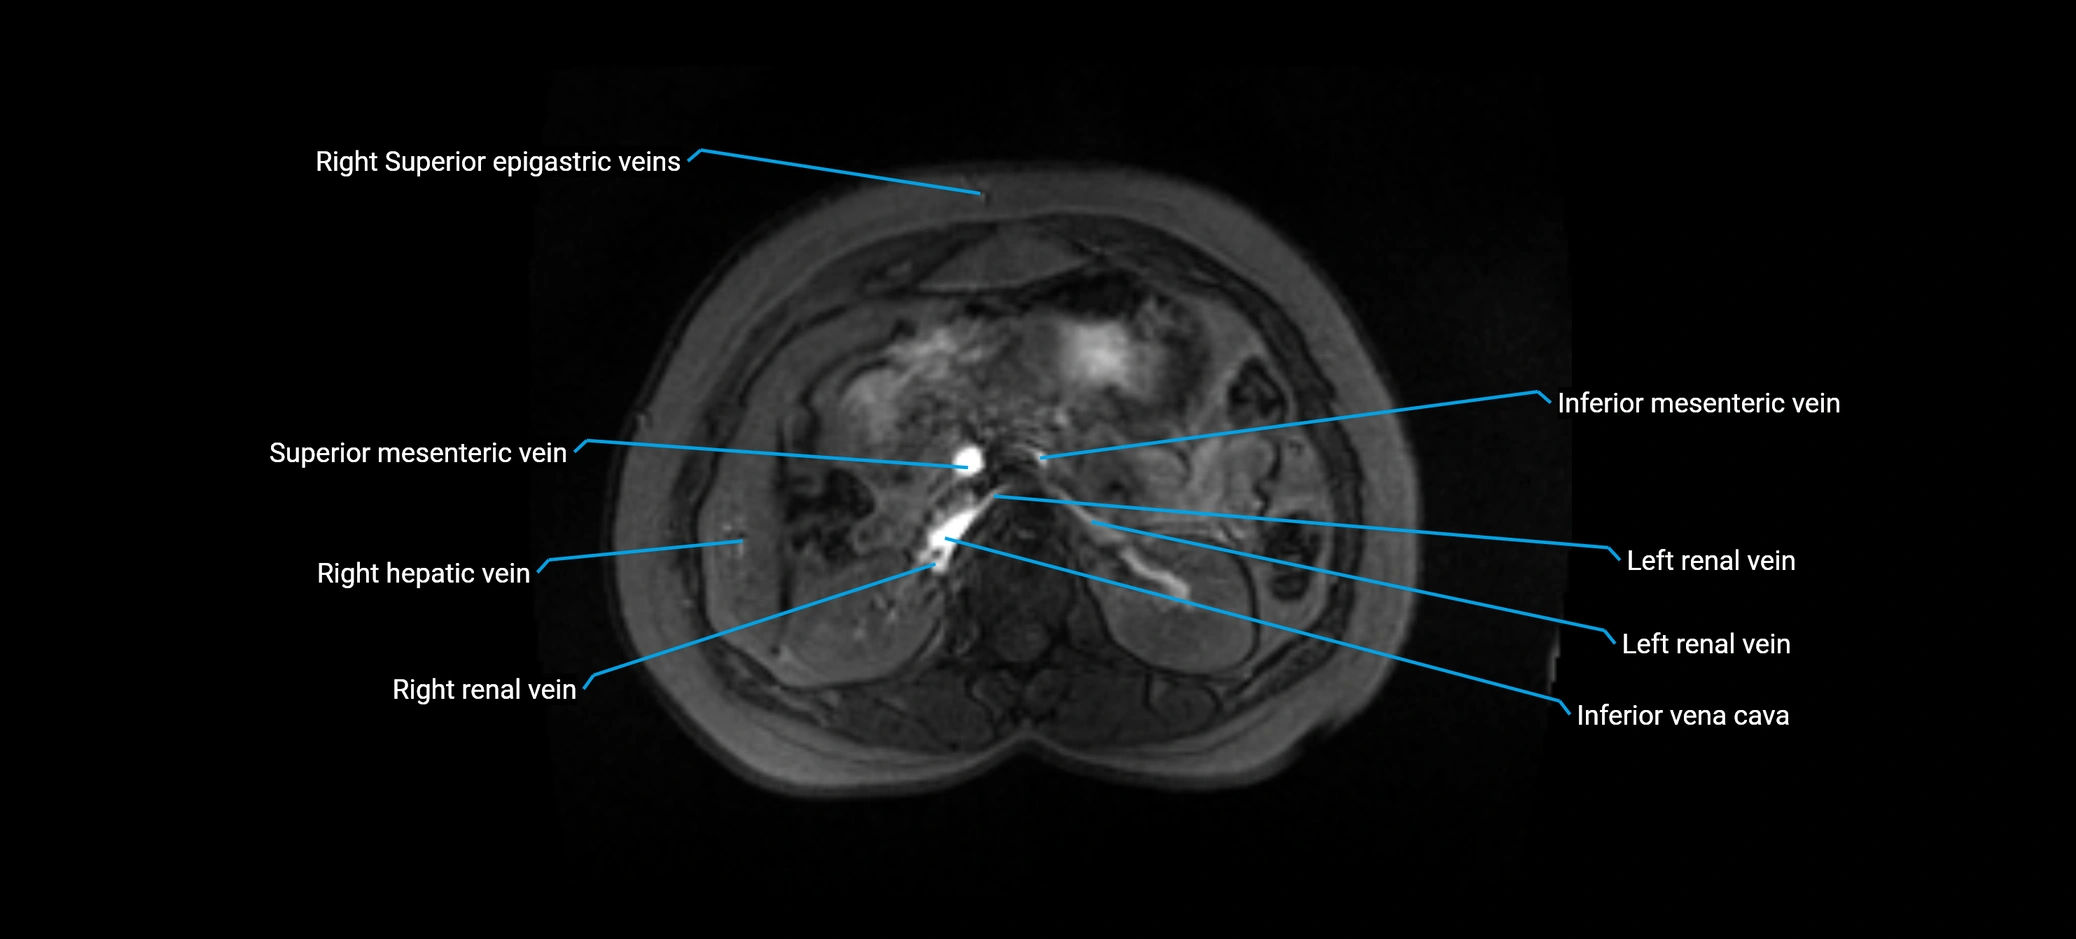

MRI image

image